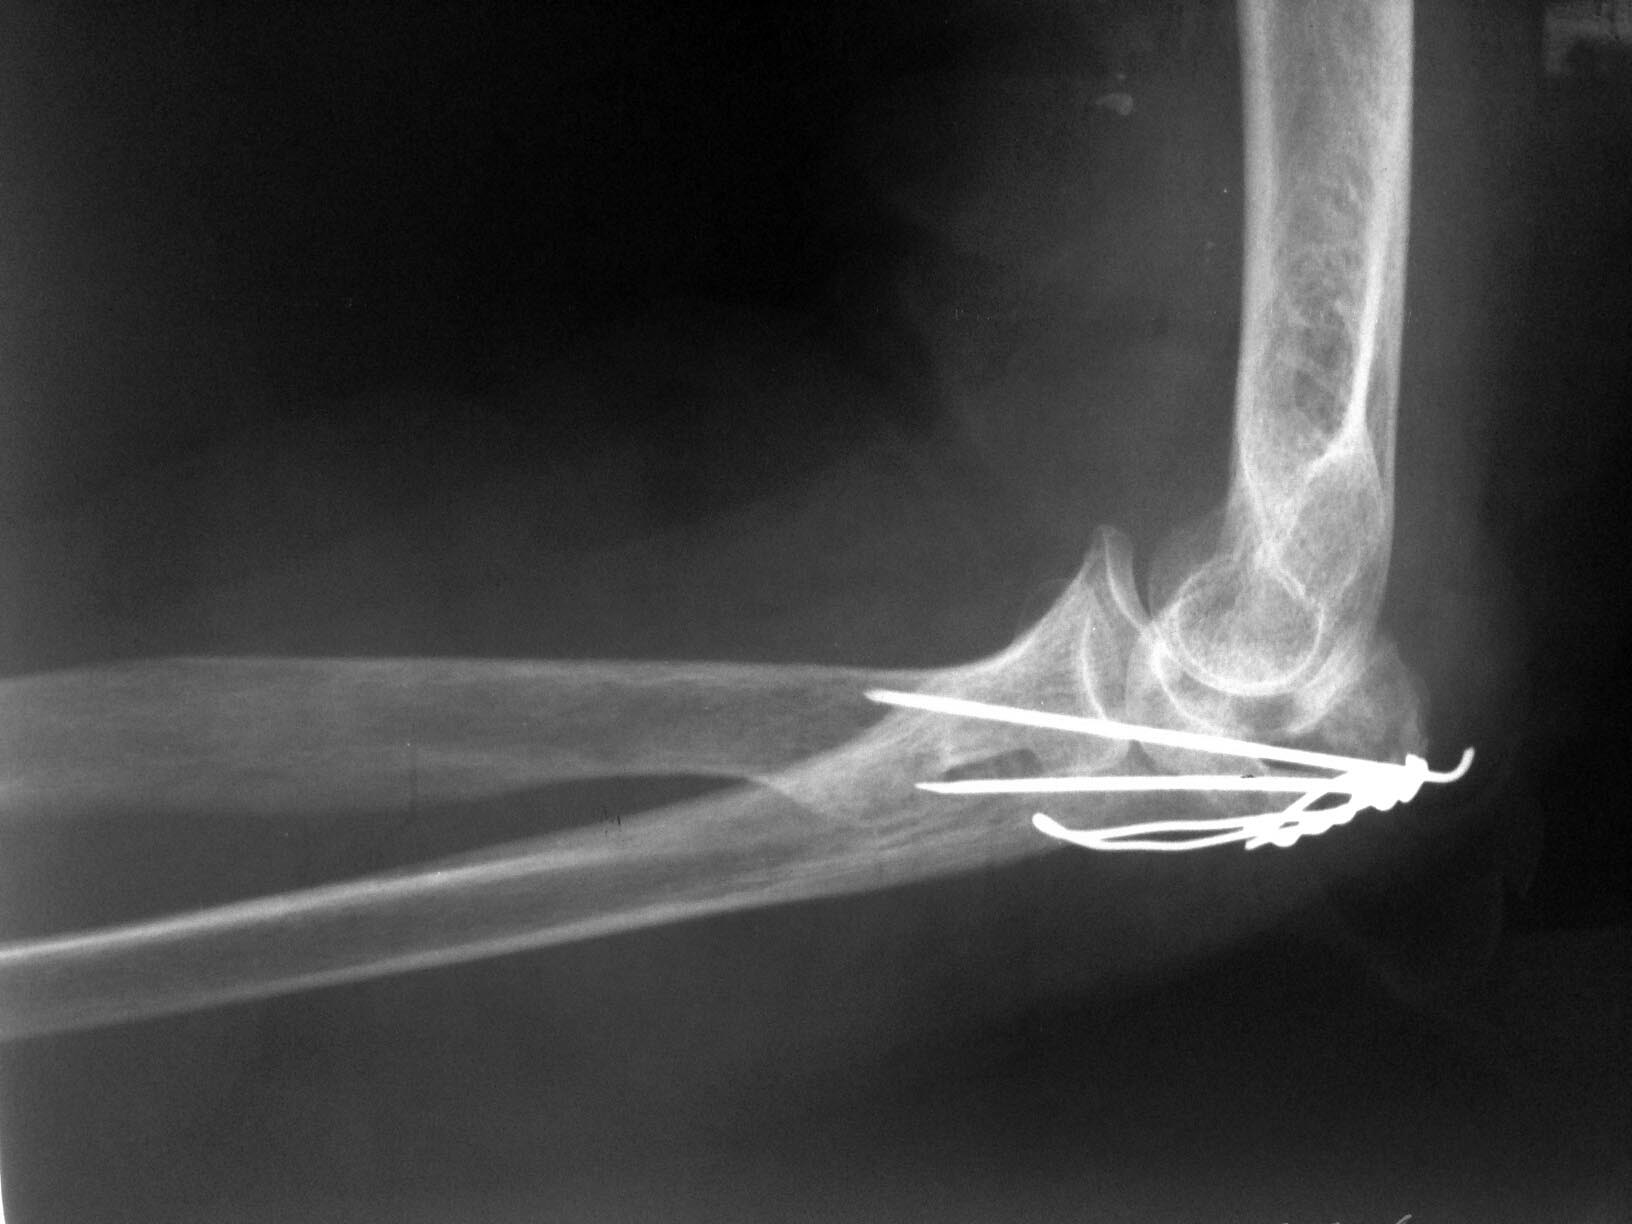

В послеоперационном периоде под личным контролем проводилась разработка движений в суставах правой верхней конечности. Рана зажила первичным натяжением. Больная выписана из клиники на 12 сутки после операции. Непосредственно в день выписки по настоянию «одного доктора» выполнена рентгенография локтевого отростка, на которой обнаружено расхождение костных отломков (на 2-3 мм (см. фото 5). Назначена врачебная внутрибольничная конференции по данному случаю, которая и проведена в ноябре 2013 года. На конференции приведены убедительные доводы об особенности клинического случая, обоснована необходимость остеосинтеза перекрестно проведенными спицами и проволокой, озвучены заключения двух известных на всю Россию профессоров-травматологов, которые подтвердили, что на рентгенограммах, сделанных в операционной «положение костных отломков локтевой кости удовлетворительное. Костные отломки в состоянии контакта друг с другом. Ось локтевой кости правильная. Учитывая преклонный возраст пациентки, следует признать возможным и допустимым выполненный вариант остеосинтеза локтевого отростка проволочной петлей и двумя спицами». Мнение «одного доктора» о необходимости повторной операции на конференции не поддержано ни одним из врачей. В решении конференции указано, что следует продолжить консервативное лечение пациентки под контролем врачей.

В последующие недели под личным контролем проводилась разработка движений в локтевом суставе. В конце декабря при контрольном осмотре в присутствии еще одного профессора и самого «одного доктора» выявлено: движения в локтевом суставе – 80/150°, пациентка довольна проводимым лечением, выполняет этой рукой все основные действия (умывание, причесывание, прием пищи и пр.), болей в локтевом суставе нет. На рентгенограммах – смещение костных отломков не увеличилось, положение металлофиксаторов – стабильное (см. фото 6). Промежуточный функциональный результат вполне удовлетворительный (фото 7,8). В настоящее время разработка движений в локтевом суставе продолжается.

4) Вероятно, следует напомнить, что продольная (по оси локтевой кости) компрессия в случае раздробления костных отломков недопустима. Именно в связи с этим проведение двух спиц параллельно друг другу со стягивающей петлей является противопоказанием при многооскольчатых (и тем более раздробленных переломах). Проведение двух спиц не параллельно, а перекрестно друг к другу как раз и не дает компрессии в момент натяжения петли. В свою очередь, проволока в этом случае выполняет роль стабилизатора положения одновременно и спиц, и промежуточных костных отломков, предотвращая смещение их в стороны. Подтверждением этому являются этапные рентгенограммы (выполненные в конце декабря), на которых отмечено стабильное положение костных отломков и металлофиксаторов, несмотря на разработку движений в суставе.